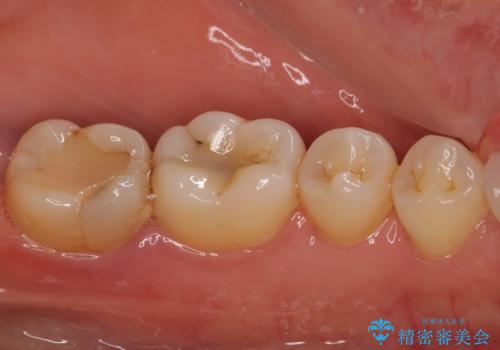

- 神経が取り除かれた歯が欠けてしまったとのことで来院された患者様です。

破折線が歯肉の中、深いところにまで及んでいる場合には歯周外科の適用となることを伝えた上で、補綴治療を行うこととしました。

破折部位を除去したところ、外科処置が必要な深さまで破折線が及んでいなかったため、速やかにジルコニアクラウンにて補綴を行うことになりました。

神経が取り除かれた歯、特に奥歯では、歯の破折が起こりやすいので、クラウンによる補綴治療が必要であることを実感した治療でした。